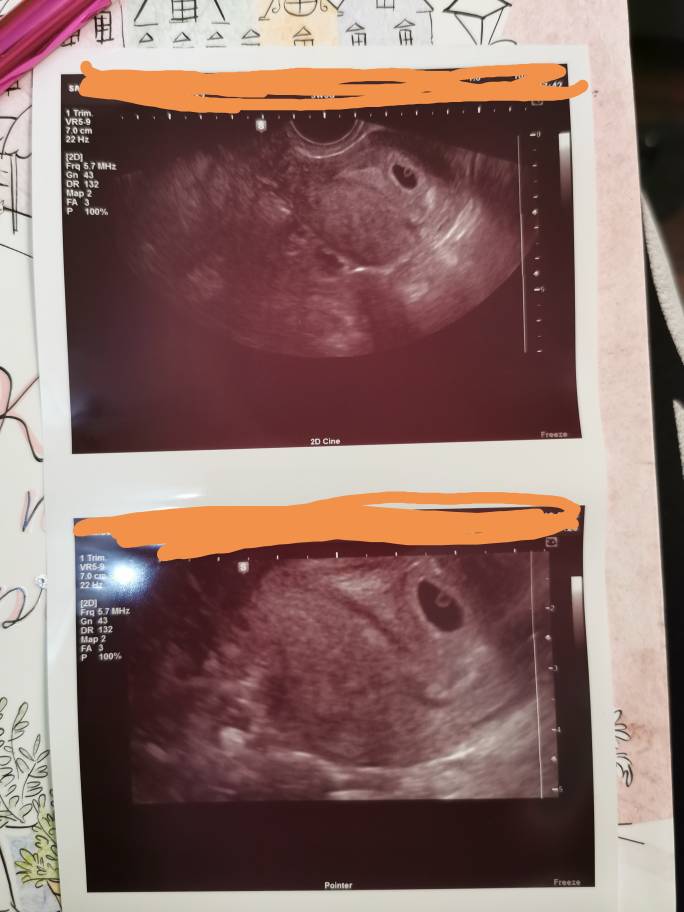

Dziewczyny ja w pierwszej ciąży z synem latałam prywatnie do ginekologa najpierw co tydzień a później co dwa tygodnie bo ciagle się stresowałam ze coś jest nie tak. Nie miałam żadnych objawów albo zle się czułam i tak w kółko. A ciąża rozwijała się książkowo. No i powiedziałam sobie ze w tej ciąży mniej stresu - objawy mogą się różnie pojawiać i znikać dopóki nie ma plamien nie będę się martwić - ta jasne [emoji23][emoji23][emoji23] dopóki wczoraj nie zobaczylam tego maleńkiego serduszka to codziennie nerwy mnie zjadały, już sobie wkręcalam najczarniejsze scenariusze. Nie da się nie denerwować kiedy nam zależy...